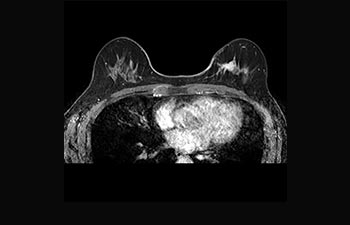

Breast lesion